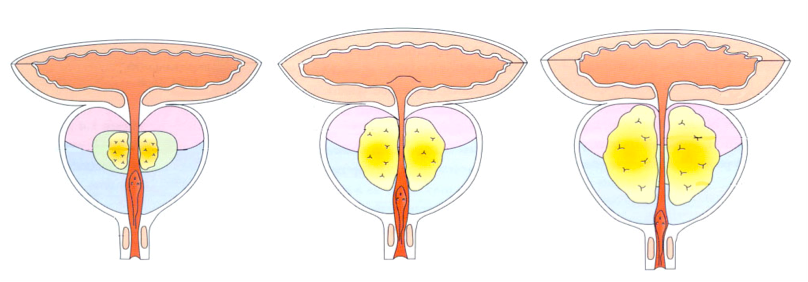

Простата, обычно ассоциируемая с мужским здоровьем после полового созревания, также присутствует у детей, хотя и в значительно меньших размерах. Этот орган, расположенный под мочевым пузырем и окружающий уретру, играет роль в выработке жидкости, которая составляет часть семенной жидкости. Несмотря на то, что проблемы с простатой у детей встречаются редко, понимание её развития и потенциальных патологий важно для ранней диагностики и лечения.